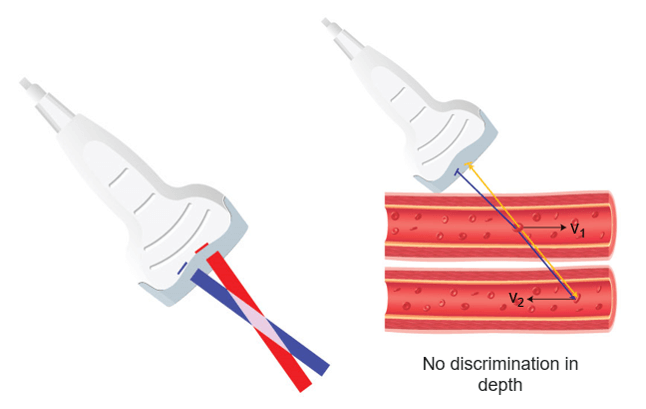

Continuous Doppler

What is the Principle of continuous Doppler?

Continuous-wave (CW) Doppler devices consist of a handheld unit with an integrated speaker that is connected to the transducer. The transducer consists of two piezoelectric elements: one element acts as a continuous transmitter (Ft) and the other one acts as a continuous receiver (Fr). Continuous Doppler continuously emits ultrasound and the frequencies reflected by the red blood cells are thus analyzed continuously.

It is important to keep a constant angle between the ultrasound beam and the vector of the red blood cell flow to collect a Doppler signal whose frequency variations exclusively reflect the changes in the blood velocity. Continuous-wave (CW) Doppler can measure very high velocities, but it is unable to pinpoint where on the scan line they come from.

The main disadvantage of these continuous emission devices is their inability to discriminate between two vessels at different depths. Despite this disadvantage, continuous Doppler devices are effective in studying the permeability of blood vessels or fetal heart function.